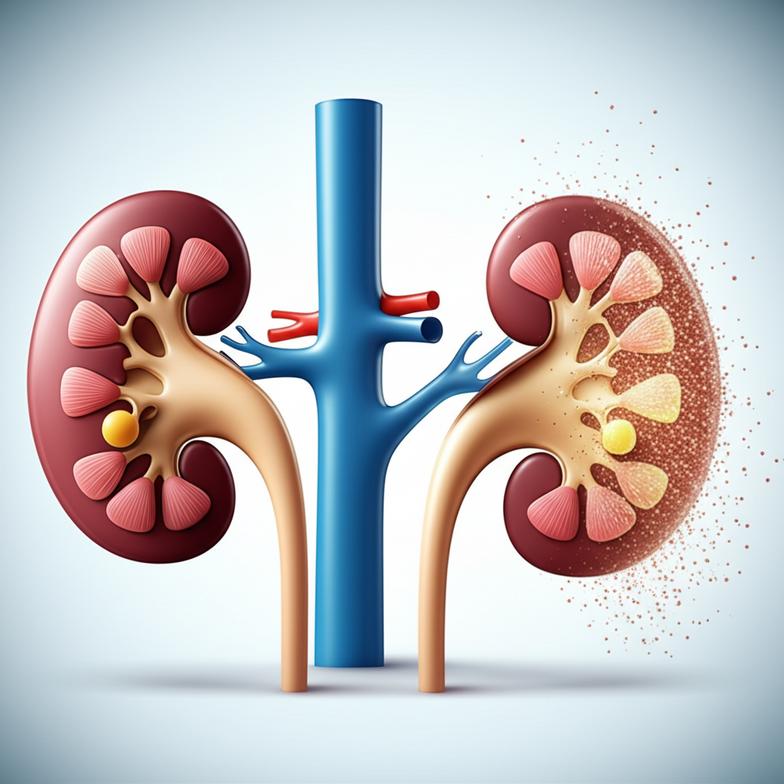

นอกจากนี้ โรคเรื้อรังหลายชนิดก็เป็นตัวเร่งสำคัญที่ทำให้ไตเสื่อมเร็วขึ้น โรคเบาหวานและความดันโลหิตสูงที่ไม่ได้รับการควบคุมที่ดี ถือเป็นสองสาเหตุหลักที่ทำลายหลอดเลือดฝอยเล็กๆ ในไต ทำให้ไตต้องทำงานหนักเกินไป ส่งผลให้โครงสร้างและหน้าที่ของไตเสียหายในที่สุด การทำความเข้าใจกลไกเหล่านี้อย่างลึกซึ้งจะช่วยให้เราสามารถเข้าถึงการดูแลที่ตรงจุดมากขึ้น และเป็นการเตรียมความพร้อมในการรับมือกับความท้าทายด้านสุขภาพนี้ได้อย่างมีเหตุผล การป้องกันและชะลอความเสื่อมจึงเป็นสิ่งสำคัญสูงสุดในแนวทางเวชศาสตร์ชะลอวัย

- ภาวะน้ำตาลในเลือดสูง: ทำลายหลอดเลือดฝอยเล็กๆ ในไต ทำให้เกิดการรั่วไหลของโปรตีนและเซลล์ผิดปกติ ส่งผลต่อการกรองของเสีย

- ความดันโลหิตสูง: เพิ่มแรงดันภายในหลอดเลือดไตอย่างต่อเนื่อง ทำให้เนฟรอนต้องทำงานหนักเกินไปและเกิดความเสียหายถาวร

- การควบคุมโรคประจำตัว: เช่น เบาหวานและความดันโลหิตสูงให้อยู่ในเกณฑ์ที่เหมาะสมอย่างเคร่งครัด เพื่อลดภาระไต